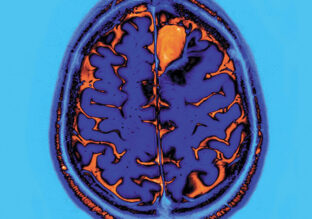

As part of the InFoR-Autism* scientific program, supported by Institut Roche, an MRI neuroimaging study investigated the links between local anatomical connectivity and social cognition in individuals with autism spectrum disorder (ASD).